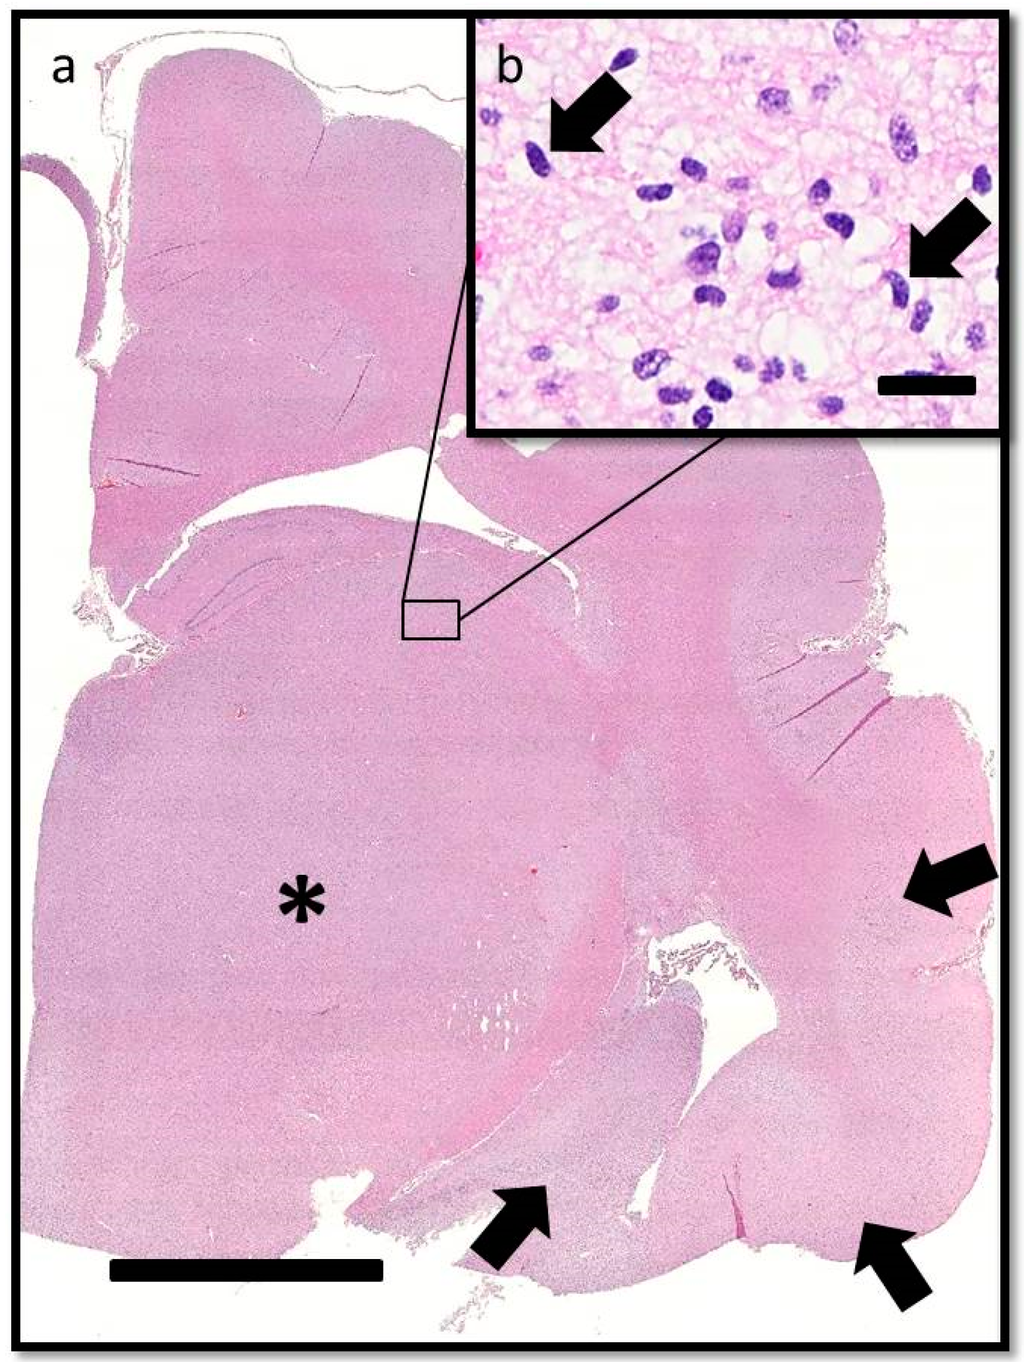

On histopathologic examination, ventral grey and white matter of the cerebrum (including the olfactory nuclei, olfactory tracts, corpus striatum, lateral septal nuclei, medial septal nuclei, thalamic nuclei and hippocampus), cerebellum, and brain stem (predominantly affecting the olivary nuclei) were bilaterally but asymmetrically infiltrated and expanded by dense sheets of neoplastic cells that merged gradually into the adjacent parenchyma, resulting in indistinct margins between normal and abnormal tissue (Figure 4a). The neoplastic cells had indistinct cytoplasm, ovoid to elongated or curved hyperchromatic nuclei, and indistinct nucleoli (Figure 4b). Anisokaryosis was mild and there was one mitotic figure per 10 400× fields. Multifocally, the neoplastic cells formed secondary structures of Scherer, including foci of subpial spread (predominantly along the ventral aspect of the brainstem; Figure 5a), subependymal aggregates (Figure 5b) with multifocal extension into and expansion of the leptomeninges, and minimal perineuronal satellitosis (Figure 5c). The neoplastic cell population was negative for Olig2, GFAP, Iba1, CD3, and Pax5. Scattered among these cells were variable numbers of GFAP-positive astrocytes, Olig2-positive oligodendrocytes, and Iba1-positive microglia. All examined sections of spinal cord were histologically unremarkable. Based on the cellular morphology, immunolabeling characteristics, and anatomical location, a diagnosis of gliomatosis cerebri was made.

Figure 4. Transverse section of the brain at the level of the interthalamic adhesion. (a) Subgross photomicrograph showing loss of general anatomical detail within the thalamic nucleus and internal capsule due to a poorly delineated neoplastic mass (asterisk). Neoplastic cells also obscure the sylvian gyrus, hippocampus, and intervening parenchyma (arrows). HE. Bar = 5 mm. (b) Inset of (a). The neoplastic cells have indistinct cytoplasm, ovoid to elongated or curved hyperchromatic nuclei, and indistinct nucleoli (arrows). HE. Bar = 20 μm.